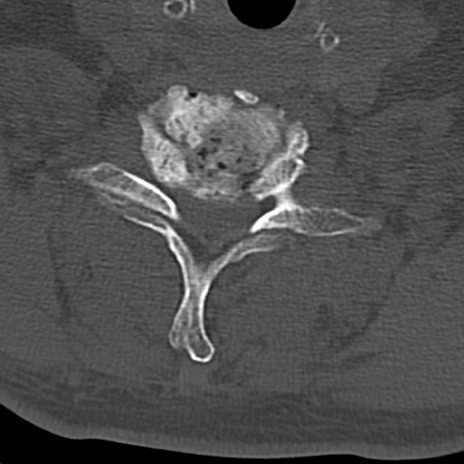

頚椎CT

横断像